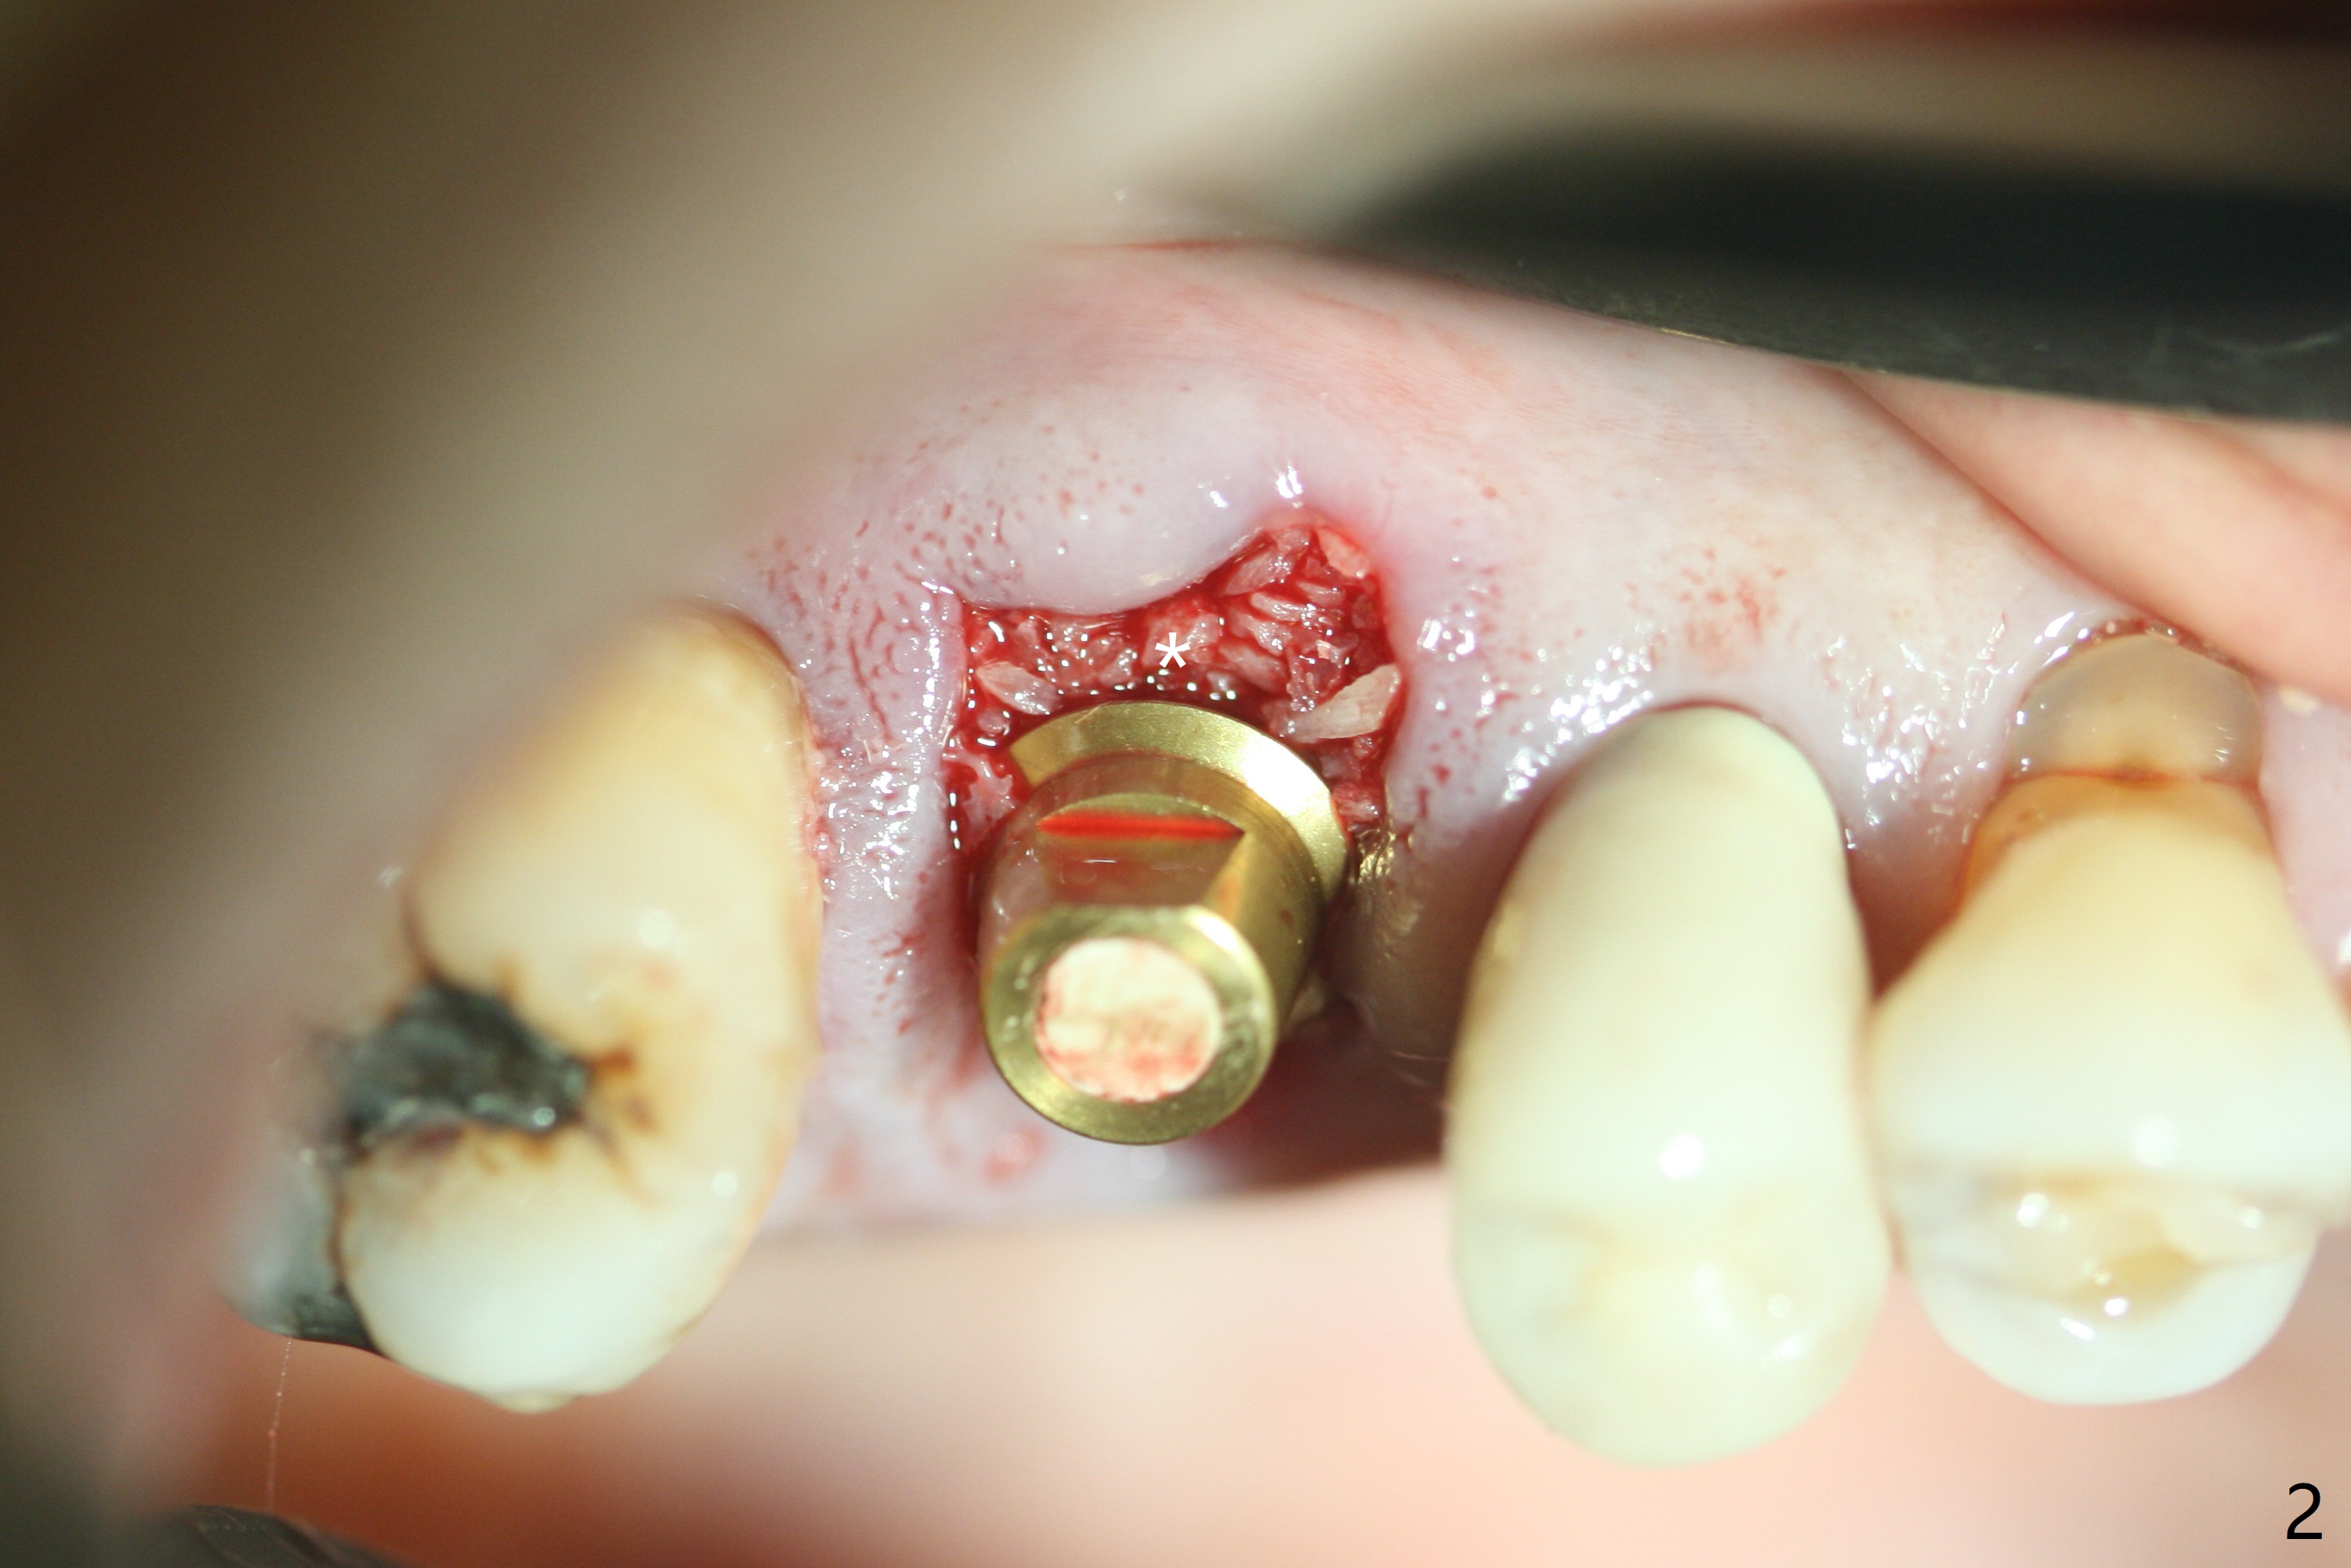

A 5x10 mm implant is placed at #3 according to drill sequence except 4.5x10 mm drill having to be used (plan: underdrilling using 4.0x10 mm as the last one) because of dense bone. Insertion torque is >50 Ncm. Although the implant apparently penetrates the sinus floor (Fig.1), the bottom of the osteotomy is intact before implant placement. In addition, the 12 mm bone trimmer does not touch the septal bone, while 2.2x8.5 mm drill starting to remove bone. In spite of using the largest cementation abutment (6.5 mm), the buccal (Fig.2) and palatal sockets with bone graft (*) are exposed. An immediate provisional (Fig.3 P) is fabricated for remaining socket closure. The buccal gingiva appears to have receded relative to the abutment margin nearly 4 months postop (Fig.4). The mesial crestal bone defect seems to be repairing (Fig.5 (*),6). The abutment later changes to a 5.7x5.5(2) mm one with margin modification buccomesiolingually before impression.